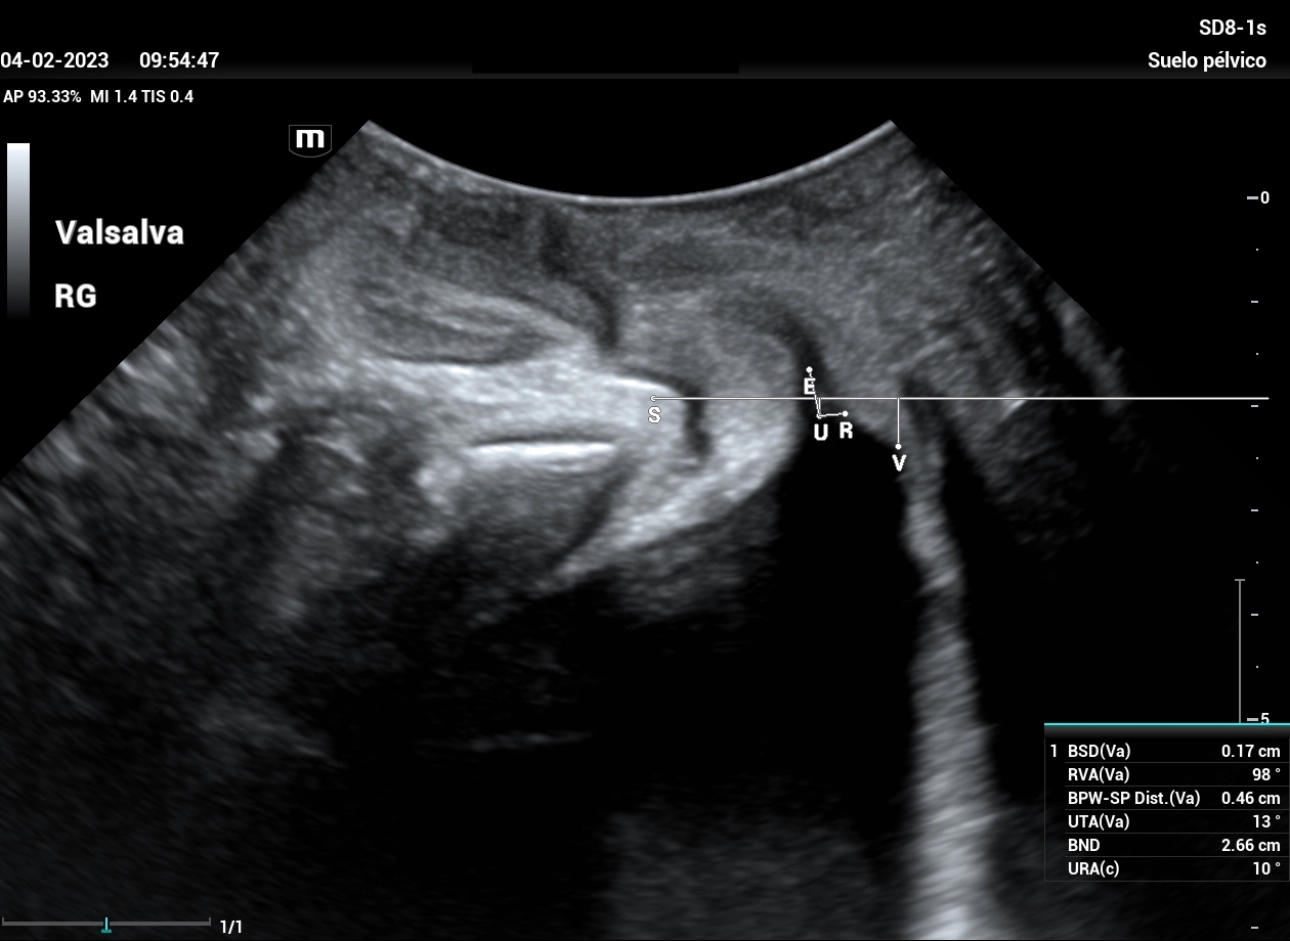

A study was carried out with filling bladder of 300 ml. The reference line is set at the inferior margin of the symphysis pubis, giving a total result of Bladder neck descent (BND) of 28mm, a UTA angle of 3º and a beta angle (RVA) of 130º (Figure 1), both within normal parameters, we performed the Valsalva maneuver showing a 26mm descent, and after maneuvering of Valsalva (Figure 2) a UTA angle of 13º (10º rotation) is observed, RVA of 98º.

stress-urine-fig2

Figure 2: Mid-sagittal section study of the pelvic floor in Valsalva maneuver. The descent of the bladder floor can be observed with respect to Figure 1, as well as the change in the angle of the urethra. Both changes do not justify, due to the values expressed, they do not justify a surgical intervention.